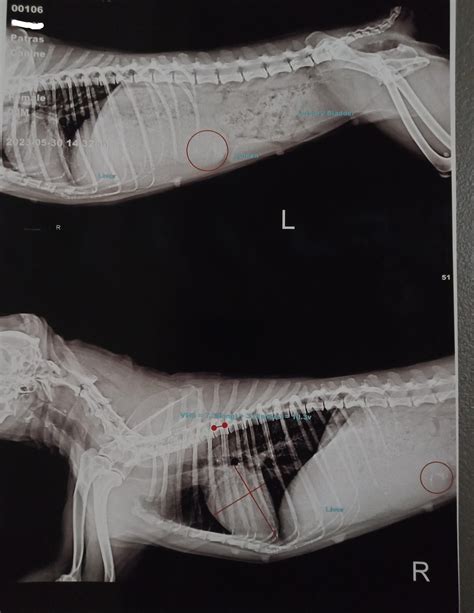

AI Will Soon Interpret Every Cat Radiograph In Seconds